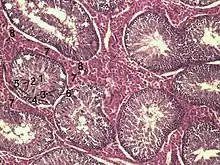

En coupe histologique des testicules après coloration PAS (periodic acid Schiff), les spermatogonies Ad (le d désignant dark) sont noirs et les spermatogonies Ap (p désignant pâle) sont claires.

- Ad : noyau sombre (dark), vacuoles nucléaires, cellule souche de la spermatogenèse, en contact avec la membrane basale, le cytoplasme contient du glycogène. Elles se divisent et donnent des spermatogonies Ap ou des Ad pour le renouvellement. Elles subissent une division hémiplastique ;

- Ap : noyau pâle, sans vacuole nucléaire. Par mitose donne des spermatogonies B (division hétéroplastique) ;

- B : noyau à chromatine en agrégat périphérique, contact avec membrane basale moins important que pour Ad ou Ap. Se divise et donne les spermatocytes I (division hétéroplastique). Possède une chromatine mottée et irrégulière.